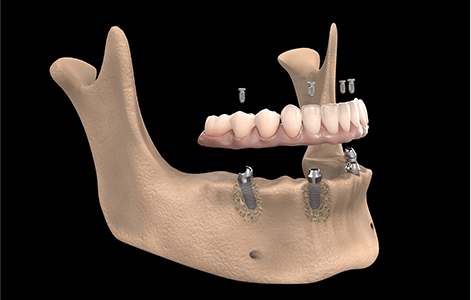

All-on-4(オールオン4)の症例数が

200例以上

オールオン4とは、総入れ歯をお使いの方や多くの歯を失った方のためのインプラント治療法です。

最少4本のインプラントで12本の歯を固定することができます。

欠損した歯が1本の場合の治療と変わらず、抜歯からインプラントの埋入、仮歯の装着までを最短1日で行うことが可能です。

当院では、200症例を超える経験豊富な歯科医師が安心の治療を提供いたします。

- インプラントの本数が少なく済むので、身体の負担や費用が抑えられる

- 手術当日から正常に咀嚼することができる

- 機能面・審美面ともに優れている

- 固定されているので外れる心配がない